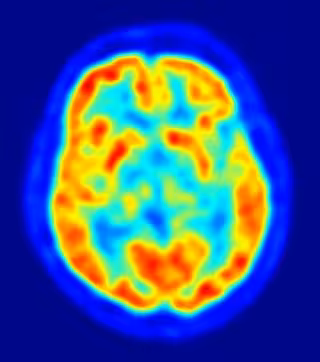

La capacidad de percibir la realidad en tres dimensiones se desarrolla en la corteza cerebral temporal inferior, donde la actividad neuronal en esta región crea una representación del objeto donde se capta además su profundidad, según un estudio llevado a cabo por expertos de la Universidad de Leuven en Bélgica.

El hallazgo, publicado en la revista 'Neuron', ha sido realizado en primates. "La corteza temporal inferior es responsable del reconocimiento de objetos. Tanto en monos como en humanos, cuando existe una lesión en ella se puede padecer agnosia, la incapacidad para reconocer objetos o estímulos ya aprendidos", aclara Janssen.

Los investigadores estimularon grupos de neuronas en la corteza temporal inferior con pequeñas descargas mientras trataban de decidir si una superficie era cóncava o convexa. "Al observar un balón de fútbol, por ejemplo, inmediatamente sabemos que tiene profundidad, que no es plano sino convexo y con estructura tridimensional", explica.